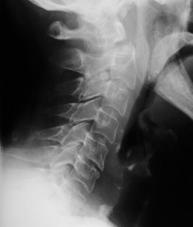

TRAUMA CERVICALA

Incidenta laterala Incidenta

laterala Incidenta

antero-posterioara

Aspect normal Imagine

incompleta Aspect

normal